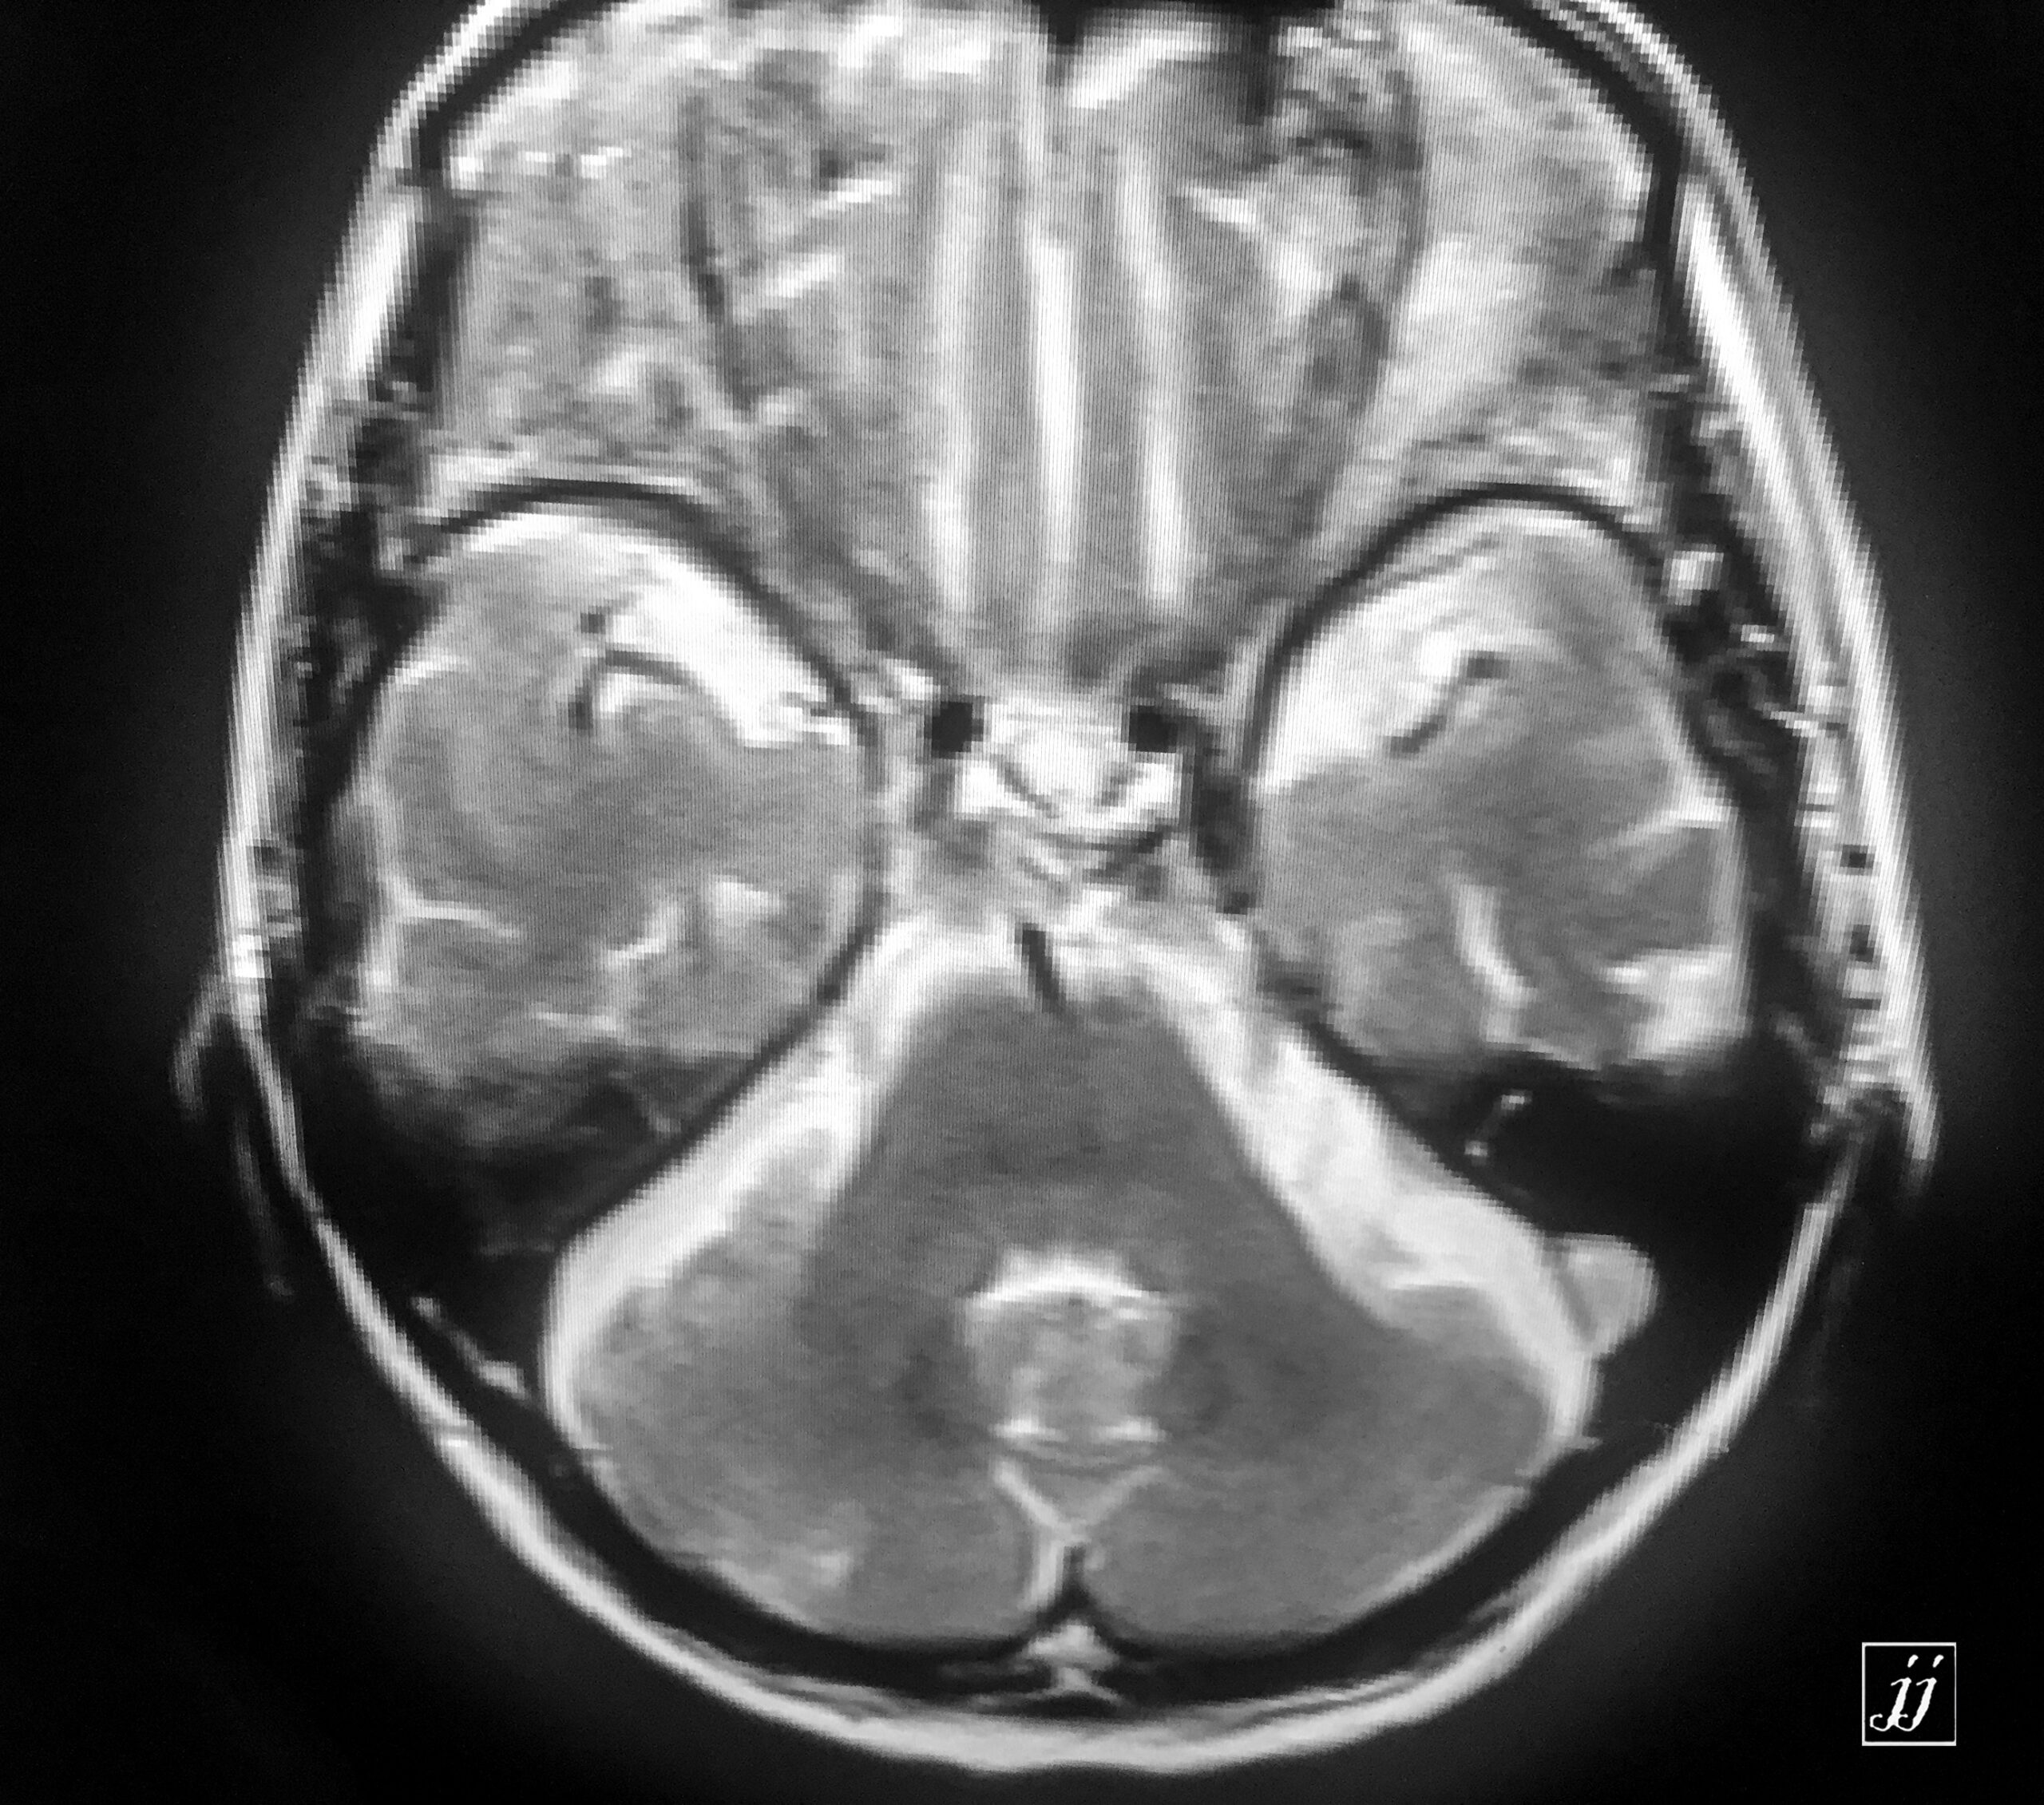

Brain- left mastoid abscess (7)